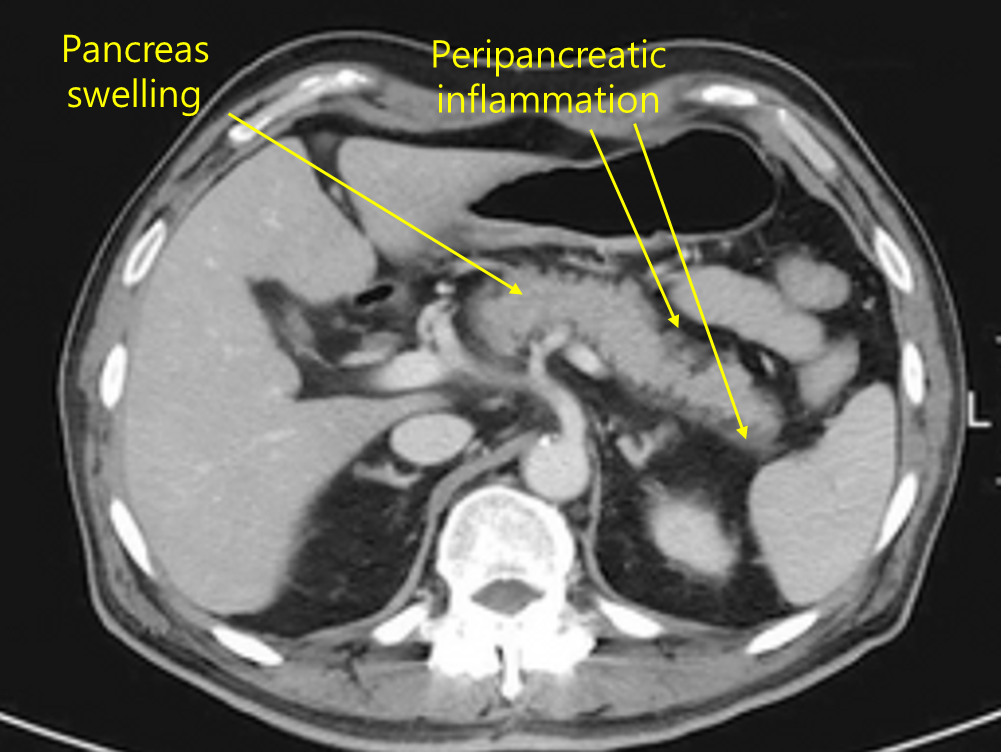

58세 남자가 2일 전부터 윗배가 아파서 병원에 왔다. 통증은 등으로 뻗치고 수 시간 지속되었으며, 등을 구부린 상태로 옆으로 누우면 나아진다고 한다. 혈압 100/70mmHg, 맥박 100회/분, 호흡 20회/분, 체온 37.8℃이다. 복부 청진에서 장음은 감소되어 들리고 배꼽주위 압통이 있다. 복부 컴퓨터단층촬영 사진이다. 진단은?

Img | CT: 이자 주위 염증, fluid collection |

수 시간 지속되고 등으로 방사되며, 몸을 구부리거나 옆으로 누우면 호전되는 통증은 급성 췌장염의 특징적인 양상이다. 복부 CT에서 췌장 주위 염증과 액체 저류 소견이 확인되므로 급성 췌장염을 진단할 수 있다.

진단 | • US: 담석, 담관확장 확인 • CT: 췌장 실질의 edema, 췌장 근처 조직의 inflammation |